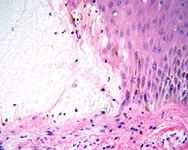

Fibrin and eosinophils are present in the blister cavity

From the collection of Dr Vesna Petronic-Rosic

Fibrin network is present in the blister cavity while the dermal infiltrate contains many eosinophils